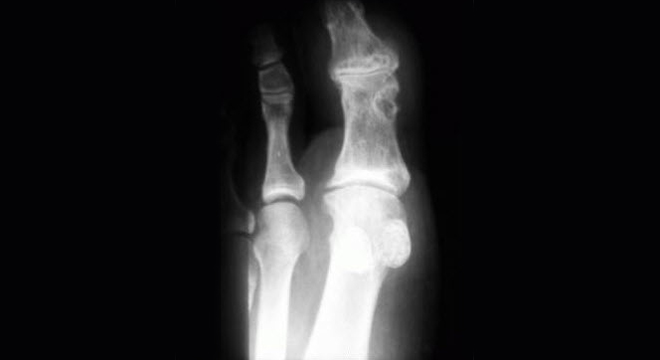

Gicht: Sichtbare Langzeitschäden in den Gelenken

• Röntgenuntersuchung: Betroffene Gelenke weisen Langzeitschäden auf